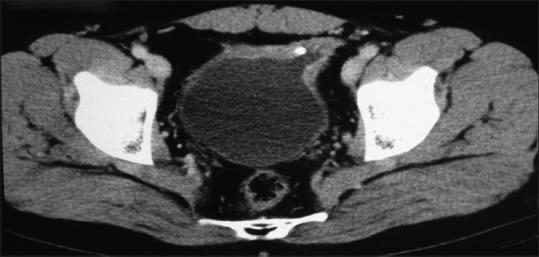

Along with advantages, evolving surgical techniques bring unique complications. A young male developed urinary symptoms a few months after undergoing laparoscopic inguinal hernia repair. On evaluation, mesh erosion into the urinary bladder was found. Removal of mesh with repair of bladder was done. A vesico-cutaneous fistula resulted which was managed with repeat surgery. We review all such cases reported in literature; discuss the etiopathogenesis, presentation, management and possible preventive measures. To the best of our knowledge, this is only the 12th case being reported.